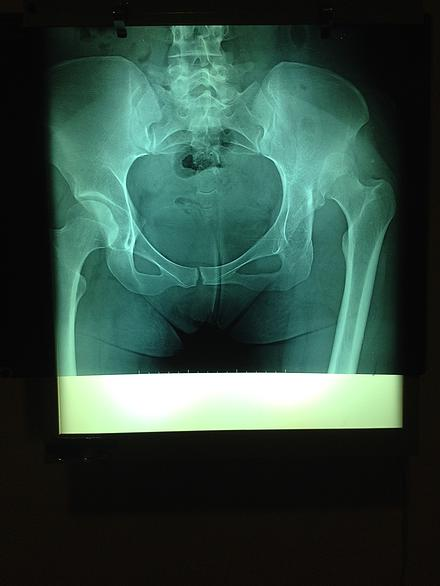

Improvisation…that is the word of the day; whether you talk to the volunteers from Santa Ines or those from the military hospital. In an unfamiliar environment, where our medical professionals are intent on maintaining the highest standard of care possible, there are a few hurdles to overcome as the patient processing is organized, OR set up and each volunteer is locating the resources they need to do their job properly. Although the day got off to a slow start and did become a late evening for some, it all came together well; five hips were completed, two hernias repaired (our hopeful 3 year old hernia did not show!) and seven cataract patients treated – a great first day – a great group of volunteers – cohesive, organized and innovative.